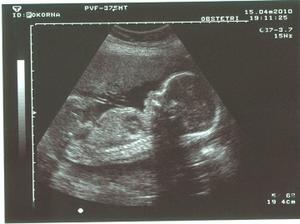

"pokorňátko" Štěpánek

1986 operativně odstraněn vejcovod

1989 těhotenství zakončené "císařským řezem" - syn Lukáš

1996 - 2009 4x laparoskopická gynekologická operace

2008 3x IUI 2008 1. IVF - ET + KET (2x transfer dvou embroušků)

2009 2. IVF - ET + KET + KET (3x transfer dvou embroušků)

V mezičase před posledním IVF, které musíme stihnout do mých 40. narozenin v dubnu 2010 ještě chceme vyzkoušet stimulovanou IUI, léky jsou doma v lednici a čeká se na příchod menstruace, která si dává načas a panuje rozladění, že IUI nestihneme do vánoc a zase další měsíc budeme nečinně "sedět"...........

8.12.2009 ŠOK!!!!!!! Na testu //, ani nevíme, kde jsme k tomu mohli přijít 🙂